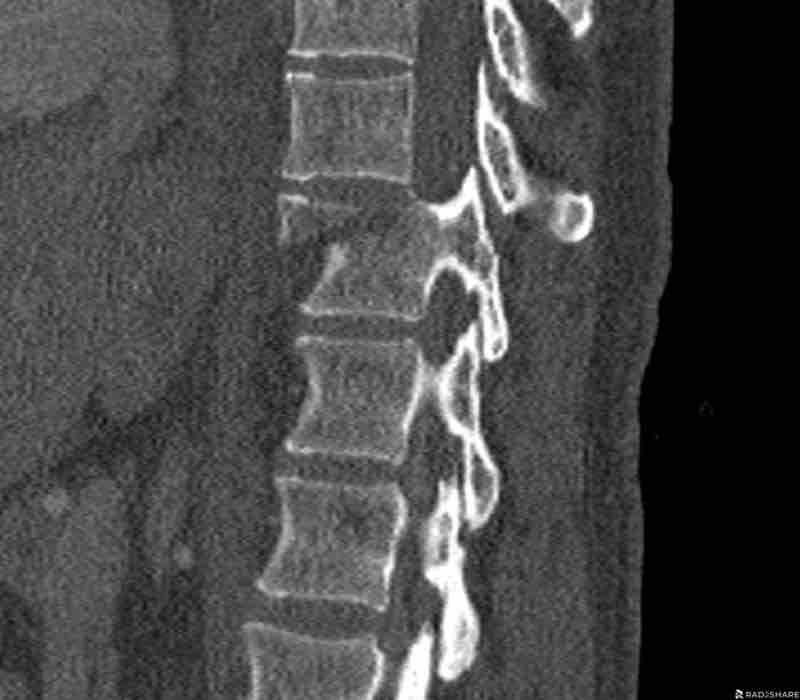

Scroll through images.

What are the findings?

Findings

- C injury? No.

- Signs of a rigid spine?

Yes (DISH), so a B3 injury is very likely. - A subtle fracture on the anterior vertebral body (arrows).

- No separation, probably due to positioning of patient in the scanner

Conclusion

Injury type B3.